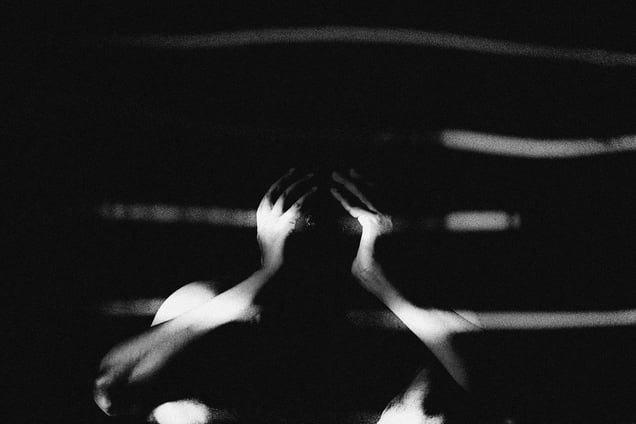

This is an ongoing personal documentation of my chronic pain – migraine. Migraine is considered a regular headache yet the sufferer had to endure 4-5 helpless hours of pain and I have been experiencing this pain for last 20 years. This project is a continuous portray of every attack I endured over the last few years. I'm currently photographing these moments with my camera and my mobile device. The purpose of this essay is to depict the underlying cause of migraine including bright light, loud sound, strong smell and its treatments such as discipline life, intake of water, brain mapping, etc. Currently, I have been healed around 80-90% thereby incorporating minor lifestyle changes and some basic medications. "Parallel Life - Migraine Chronicles" is my artistic endeavour, born from empathy and a desire to shed light on the oft-hidden agony of migraines. Through the lens of my camera, I have embarked on a visual odyssey to unveil the visceral, emotional, and deeply human journey of those grappling with this debilitating condition.